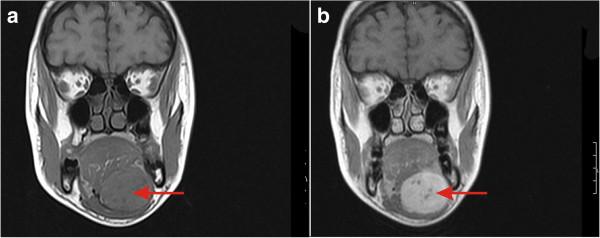

We present a rare case of microfollicular follicular adenoma in an ectopic sublingual thyroid tissue presenting as submental swelling in a euthyroid 24-year-old Dravidian woman.

Findings in this case emphasize that when confronted with a submental/sublingual mass lesion, the evaluation of thyroid function tests and ultrasonography of the neck should be included in a pre-operative workup.